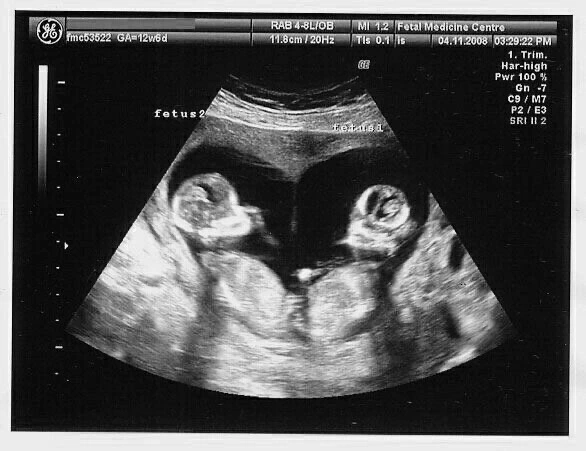

그렇다. 나는 쌍둥이로 환생했다. 아기별에서 읽었던 <환생 가이드북>에 따르면, 쌍둥이는 매일 같은 옷을 입고 같은 밥을 먹으며 자란다. 부모님의 사랑을 두고 자기들끼리 은근한 경쟁을 벌이는 ‘라이벌’이라는데, 그 싸움은 뱃속에서부터 이미 시작된 듯하다.